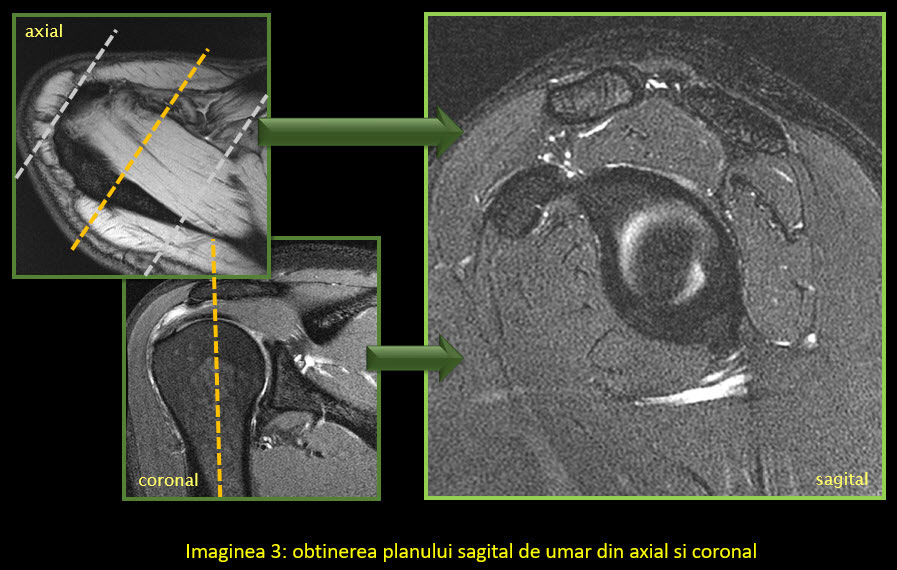

În mod normal, planurile uzual utilizate în imagistică sunt coronal, sagital și axial. În cazul umărului și majorității articulațiilor, oasele și articulațiile au o orientare specială, astfel încât se folosesc planuri modificate. Singurul plan standard este cel axial, deși poate suferi și el modificări în anumite condiții.

Utilizarea planurilor în mod corect permite evidențierea unei structuri, cum ar fi un tendon, într-o singură imagine/secțiune, fără să interfere așa numitul efect de volum parțial (adică să avem într-o imagine părți de anatomie din imaginea următoare sau precedentă). Efectul de volum parțial nu poate fi eliminat în totalitate, dar este cu atât mai mic cu cât secțiunea este mai subțire, spațiul dintre secțiuni mai mic și planul corect aliniat la anatomie.

Astfel:

• Paralel cu tendonul capului lung al bicepsului

• Perpendicular pe marginea anterioară a glenei scapulei

• Paralel/ perpendicular pe difiza humerală

• Paralele față de articulația acromio-claviculară.